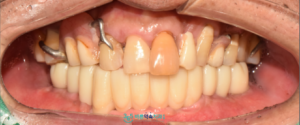

모든 치료가 마무리된 후의

구강 내 사진과 파노라마 사진입니다.

환자분께서는 임플란트 치료가

부담스러울 것이라 생각하셨지만,

과정이 비교적 편안하게

진행되었다고 말씀해 주셨습니다.

치료 이후에는

양측 저작이 한결 수월해지고

웃는 모습에도 변화가 생겨

만족감을 표현해주셨으며,

예상보다 빠르게 치료가 마무리된 점에

대해서도 긍정적으로 말씀해 주셨습니다.